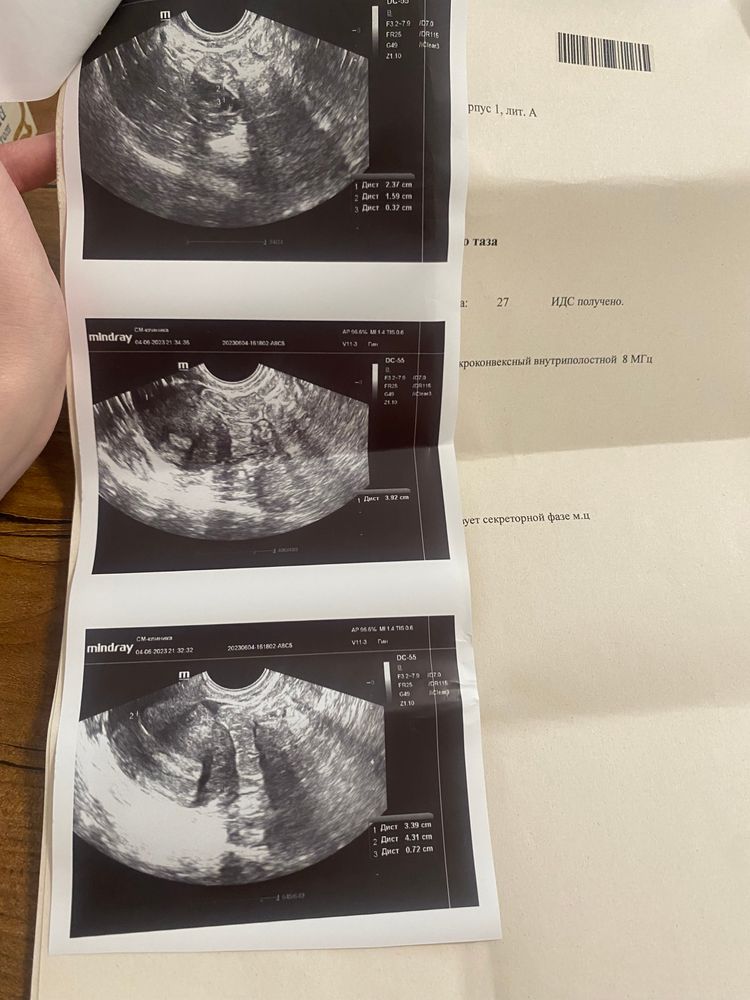

УЗИ удалось сделать, врач узи (не гинеколог) сказала, что желтого тела нигде нет. Овуляции не было и не предвидится уже (21 день цикла).

Я скинула гинекологу снимки узи и заключение, она написала: «По эндометрию как будто бы овуляция была. Если будет возможность, на этой неделе сдайте кровь на прогестерон.»